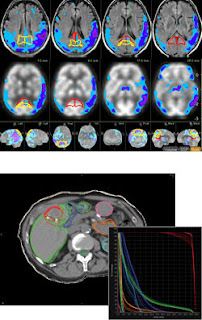

這次來介紹一下已經獲得FDA許可的APP軟體:Mobile MIM。這是由MIM SOFTWARE這家公司所開發出來的軟體,其於2001年成立,原本是生產與銷售醫療影像用軟體。先前的產品包括了整合醫院內多種影像的比較軟體,以及一些影像增強與應用之軟體。(參考下圖,影像來自http://www.mimsoftware.com/products)

該產品主要目的為對醫學影像做標記、擴散、顯示或診斷,其所適用的影像種類包括SPECT, PET, CT, 與 MRI。該產品提供無線與可攜式存取醫療影像。該產品並非取代工作站,而且僅應使用於無法存取工作站之資料時。該產品不可用於乳房攝影。